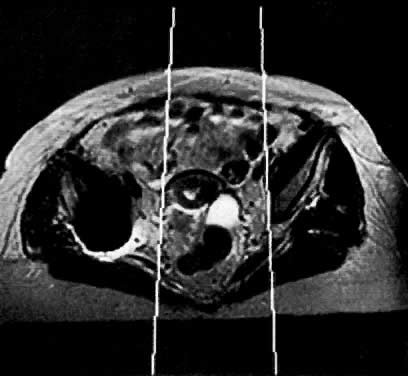

Fig. 16. A. Axial T1-weighted MRI of a stage IIB cervical carcinoma shows a mass ( m) extending from the cervical tumor ( c) in the right parametrium. B. Axial contrast-enhanced T1-weighted MRI shows enhancement of the cervical and parametrial mass after gadolinium bolus injection.(Mayr NA, Tali ET, Yuh WTC et al: Cervical cancer: Application of MR imaging in radiation therapy. Radiology 189:601, 1993)

Peritumoral inflammatory reaction can mimic parametrial involvement, causing tumor overstaging on T2-weighted imaging.33 In addition to edema, factors including volume averaging, bowel peristalsis artifact, close proximity of structures, obliquity of planes, and anatomic variations may obliterate fat planes between the tumor and the surrounding organs, thus increasing the false-positive rate, especially in advanced disease.34 Gadolinium-enhanced T1-weighted MRI techniques do not seem to improve visualization of stromal invasion of cervical carcinoma, but do improve staging in advanced cases (see Fig. 16A and Fig. 16B).35 Recent studies have shown that gadolinium-enhanced dynamic MRI may be superior to T2-weighted MRI in the evaluation of stromal invasion.12 Fat suppression techniques may also better delineate the tumor margins (Fig. 14B) and detect bladder or rectal wall invasion.36 MRI using endorectal surface coils may also prove to be a promising technique because of improved resolution over conventional MRI techniques.37